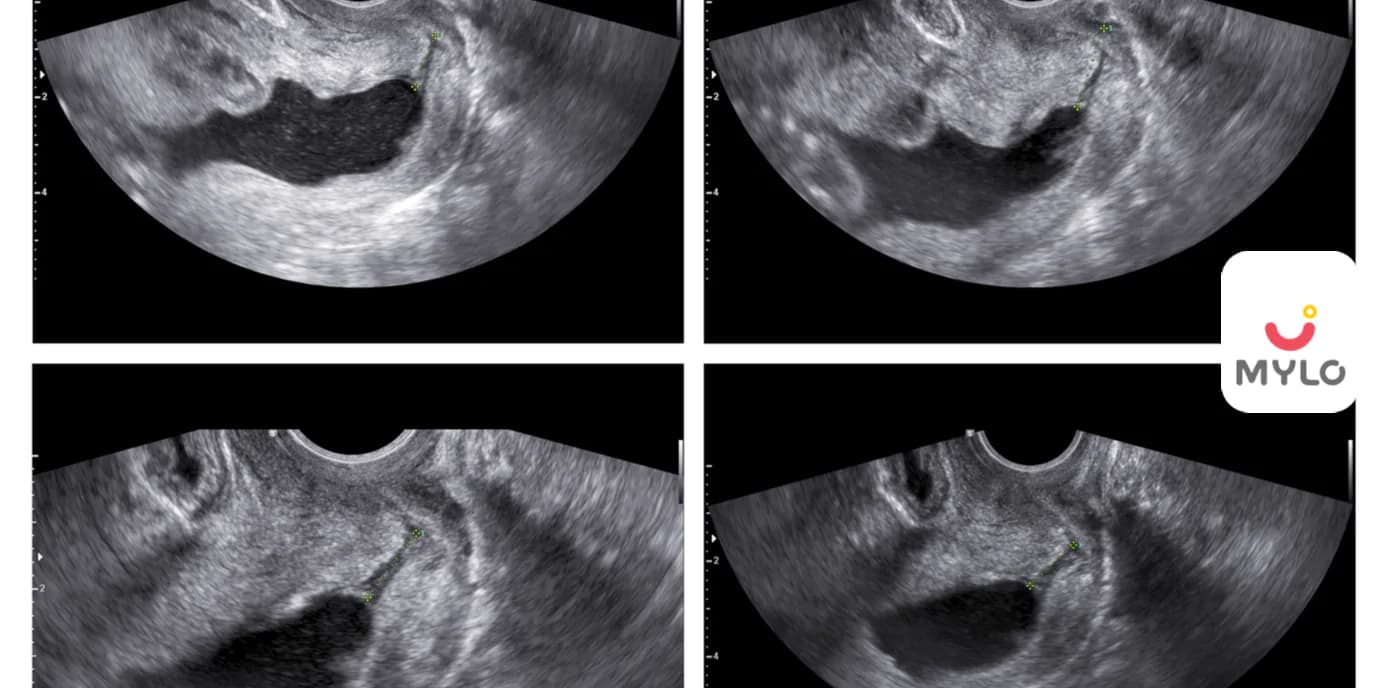

Scan & Tests can confirm your pregnancy and also monitor your baby’s development in the womb